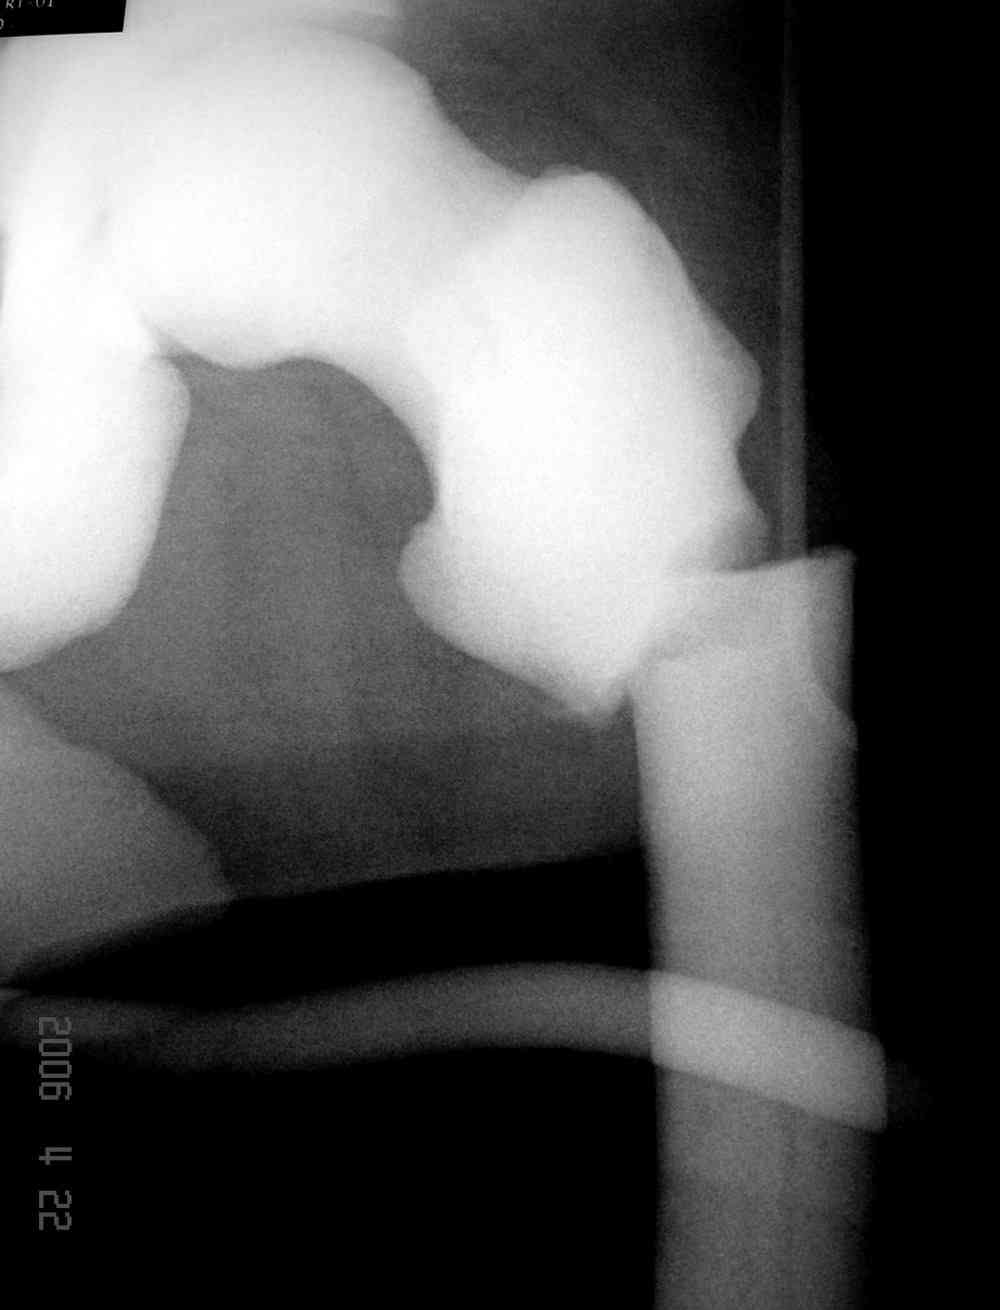

Не являюсь специалистом по костной патологии, но мне кажется, на ренгенограмме множественные мета-диафизарные образования напоминяющее змееподобных извилистых линии и периостеальные ламинирование очень напоминяет картину остеонекроза (инфаркта) костей, возможно связано с длительным применением стероидов.

При предоставлении дополнительных информации, сканнирования, МРТ и лабараторных данных можно уточнить предварительный диагноз, пока склонен к обширному костному инфаркту, и таких больных рекомендуем лечить сиптоматически.

слайды из прошлегодного случая.